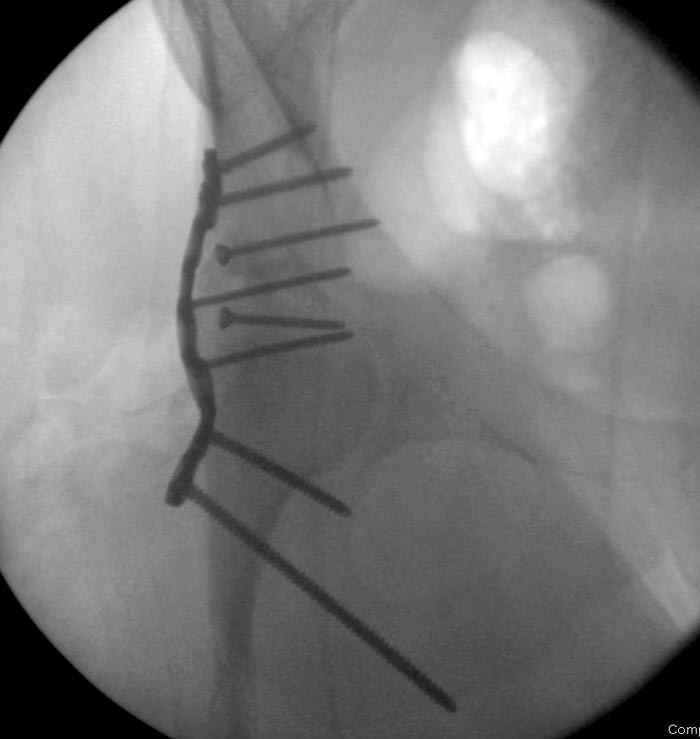

7:30 начало операции, больной на спине, попытка репозиции после анестезии N3, укладка больного на боку, доступ Kocher- Langenbeck, состояние седалищнего нерва около 2.5см кровоподтек, через joistick головка бедра приподнята, освобовождение сустава, фрагмент заднего края более 3х4 см репонирован на свое место. После промывания

сустава, репозиция вывиха (N4), фиксация фрагмента 2.7(4) мм шурупами и допольнительно реконструктивной пластиной на 8 дырок, фиксация 3.5мм шурупами проксимально и дистально.

Интраоперционные N5 косая запирательная и N6 подвздошный снимок

11:50 больной в послеоперационной, рентгенограмма N7, компьютерная томограмма в тот же день N8-10